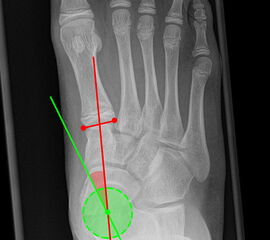

Vermessung der belasteten Aufnahmen des Fußes

Winkelmessungen am Fußskelett beziehen sich sämtlich auf belastete Aufnahmen 6. Die folgenden Aufnahmen zeigen die üblicherweise verwendeten Winkelmaße und ihre Definition. Viele Fehlstellungen des Fußes betreffen den Vor- und Rückfuß. Dies sollte bei der Beurteilung der Bilder und der Therapieplanung stets berücksichtigt werden.

Beurteilung von Fehlstellungen des Vorfußes

Zur Vollansicht und zum Lesen der Bildbeschreibung bitte die Bilder anklicken.

Gelenkflächenwinkel

DMAA (Distal metatarsal artikular angle, Syn. Gelenkflächenwinkel): Winkel zwischen der Achse des Os metatarsale I (rot) und dem Lot auf die distale Gelenkflächenebene (blau) des Os metatarsale I. Die Gelenkflächenebene (grün) wird definiert durch zwei Punkte, welche die mediale und laterale Begrenzung der Gelenkfläche definieren (Norm: <10° 5). Die Projektion des DMAA ist stark abhängig von der Rotation des Os metatarsale I 7. Daher ist bei der operativen Behandlung des Hallux valgus eine Beurteilung häufig erst nach Korrektur der Pronationsstellung des Os metatarsale I möglich. Tendenziell wird der DMAA auf präoperativen Röntgenaufnahmen überschätzt.

Beurteilung eines Metatarsus adductus

Medial wird eine Linie von der medialen Begrenzung des TMT1-Gelenks und der medialen Begrenzung des Talonavikulargelenks (TN) gezeichnet. Auf der lateralen Seite des Fußes wird eine zweite Linie von der lateralen Begrenzung des Calcaneocuboid-Gelenks (CC) zur lateralen Begrenzung des TMT5-Gelenks gezeichnet. Die Mittelpunkte beiden Linien werden verbunden (blau). Der Winkel zwischen der Achse des Os metatarsale II (rot) und dem Lot auf Verbindungslinie (grün) ist ein Maß für die Stellung des Vorfußes zur Fußwurzel. Dieser Wert dient zur Charakterisierung eines Pes adductus. Ein Pes adductus kann zu einem normwertigem Intermetatarsale I/II Winkel führen, obwohl klinisch eine ausgeprägte Hallux valgus Deformität vorliegt 8. (Norm: ±13° 9.